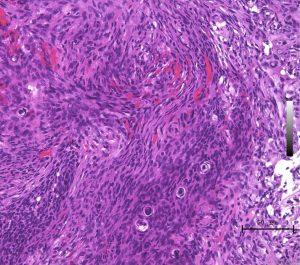

storiform pattern(長嶋和郎先生の病理教室)

紡錘形細胞が放射状に配列する所見でstoriform patten (花むしろ)、またはcartwheel (車輪)状に似た様子が見られます。軟部腫瘍であるfibrous histiocytomaで良く見られるものです。本例ではCP-angle meningiomaに見られた所見で、fibrous meningiomaの診断です。MIB-1 indexはやや高く8%でしたが、壊死や異型性は見られず、Grade 1相当とみなされます。HE x200